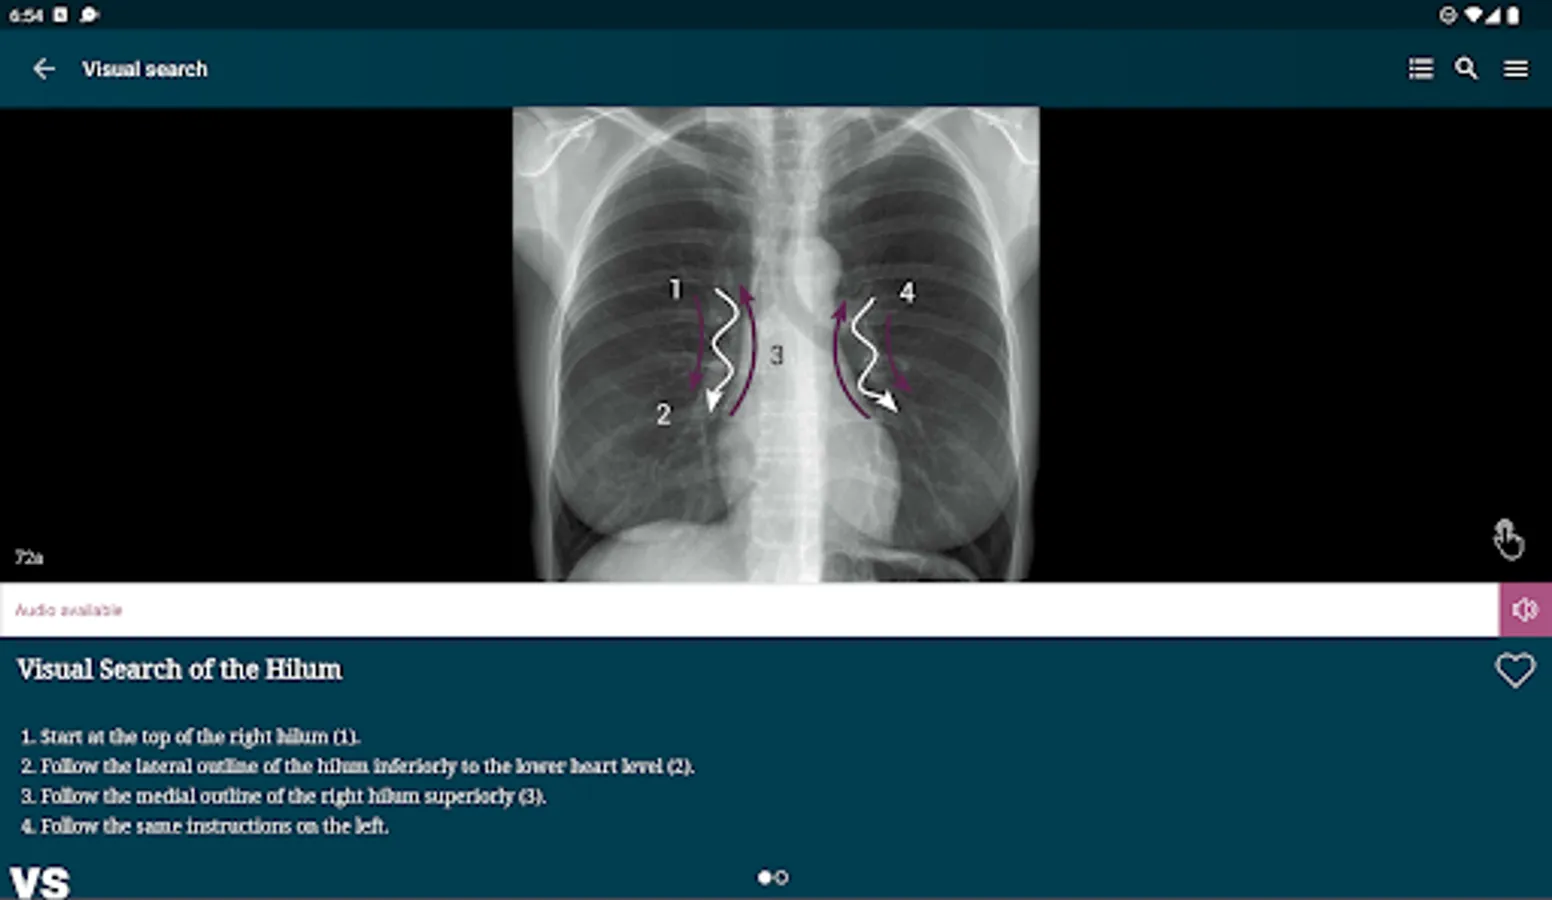

Visual Searches – 8 visual guides to illustrate the sequential checks that should be performed in a visual search of given anatomical structure or radiological zone on a chest x-ray.